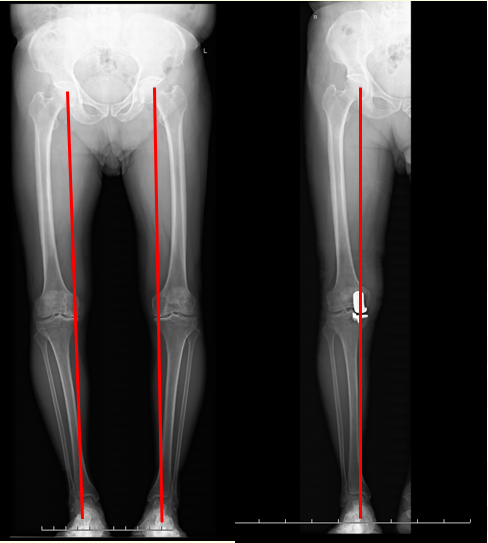

在选择治疗方式前,我们首先需要照双下肢全长负重位正侧位X线片和髌骨30°轴位X线片,可以判断是关节内畸形还是关节外畸形;必要时加照膝关节内翻或者外翻应力位正位照片,查明是膝关节内侧或者外侧软骨退变的轻重和部位。膝关节磁共振检查对于诊断半月板退变、撕裂和脱位及评估软骨的厚度方面具有一定的价值。

68岁阿叔,左膝关节疼痛2年了,他的要求是希望手术后除了不痛,还要求以后可以踢毽子和游泳,考虑到他膝关节内侧软骨磨损并不是完全磨损,结合他个人的手术期望值,治疗方式为:胫骨高位截骨术,术后第二天就下地行走,术后一个月完全恢复正常,非常满意

赖阿姨,65岁。30年前右髋关节结核做了手术,后面遗留畸形,不能行走,渐渐的继发了左膝关节疼痛,表现为膝关节外侧疼痛,外翻畸形。考虑到她还很年轻,治疗方式为:同时做了右侧人工髋关节置换术和左侧膝关节外侧单髁置换术,术后恢复顺利,1个月已经可以正常行走

71岁的陈伯,双膝疼痛10余年。X线片提示双膝是晚期骨关节炎,非常明显的顺风腿。双侧做了人工膝关节表面置换术后,术后第二天就可以下地走路,目前可以正常出行,生活健康